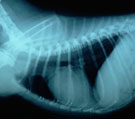

初診時。重度な呼吸困難。著明なチアノーゼ 胸部レントゲン。心基部を限局した肺浸潤影あり。 治療開始2.5時間後。呼吸症状は著しく改善した。 翌日の胸部レントゲン。浸潤影は完全に消失。

経過:受診時にはすでに発症から1時間が経過していた。体温41.6℃、および重度なチアノーゼと頻呼吸(138/分)をともなった努力性呼吸がみられ、起立不能であった。発症直前まで全く問題なかったという。心疾患等の既往もない。胸部レントゲンにて心基部に限局した肺浸潤影が認められたが気管虚脱や心陰影に異常を認めなかった。動脈血ガス分析では、pH 7.181, Pco2 63.8 mm Hg, Po2 30.3 mm Hgと重度な換気障害を伴った致死的な低酸素血症が認められた。急性の気道閉塞と臨床診断した。原因は不明だが、何かが引き金となりびまん性末梢気道収縮が起きていた。徹底した気管支拡張を目的に酸素吸入と、注射および吸入によるステロイド投与を行った。治療開始2.5時間後、体温37.5℃、呼吸数66/分と急性呼吸不全症状は著しく改善し、一般状態は正常になった。翌日、胸部レントゲンにて浸潤影は完全に消失し、血液ガス分析もpH 7.428, Pco2 37.3 mm Hg, Po2 101.5 mm Hgと全く正常となり退院となった。このような発作症状は初めて経験したという。